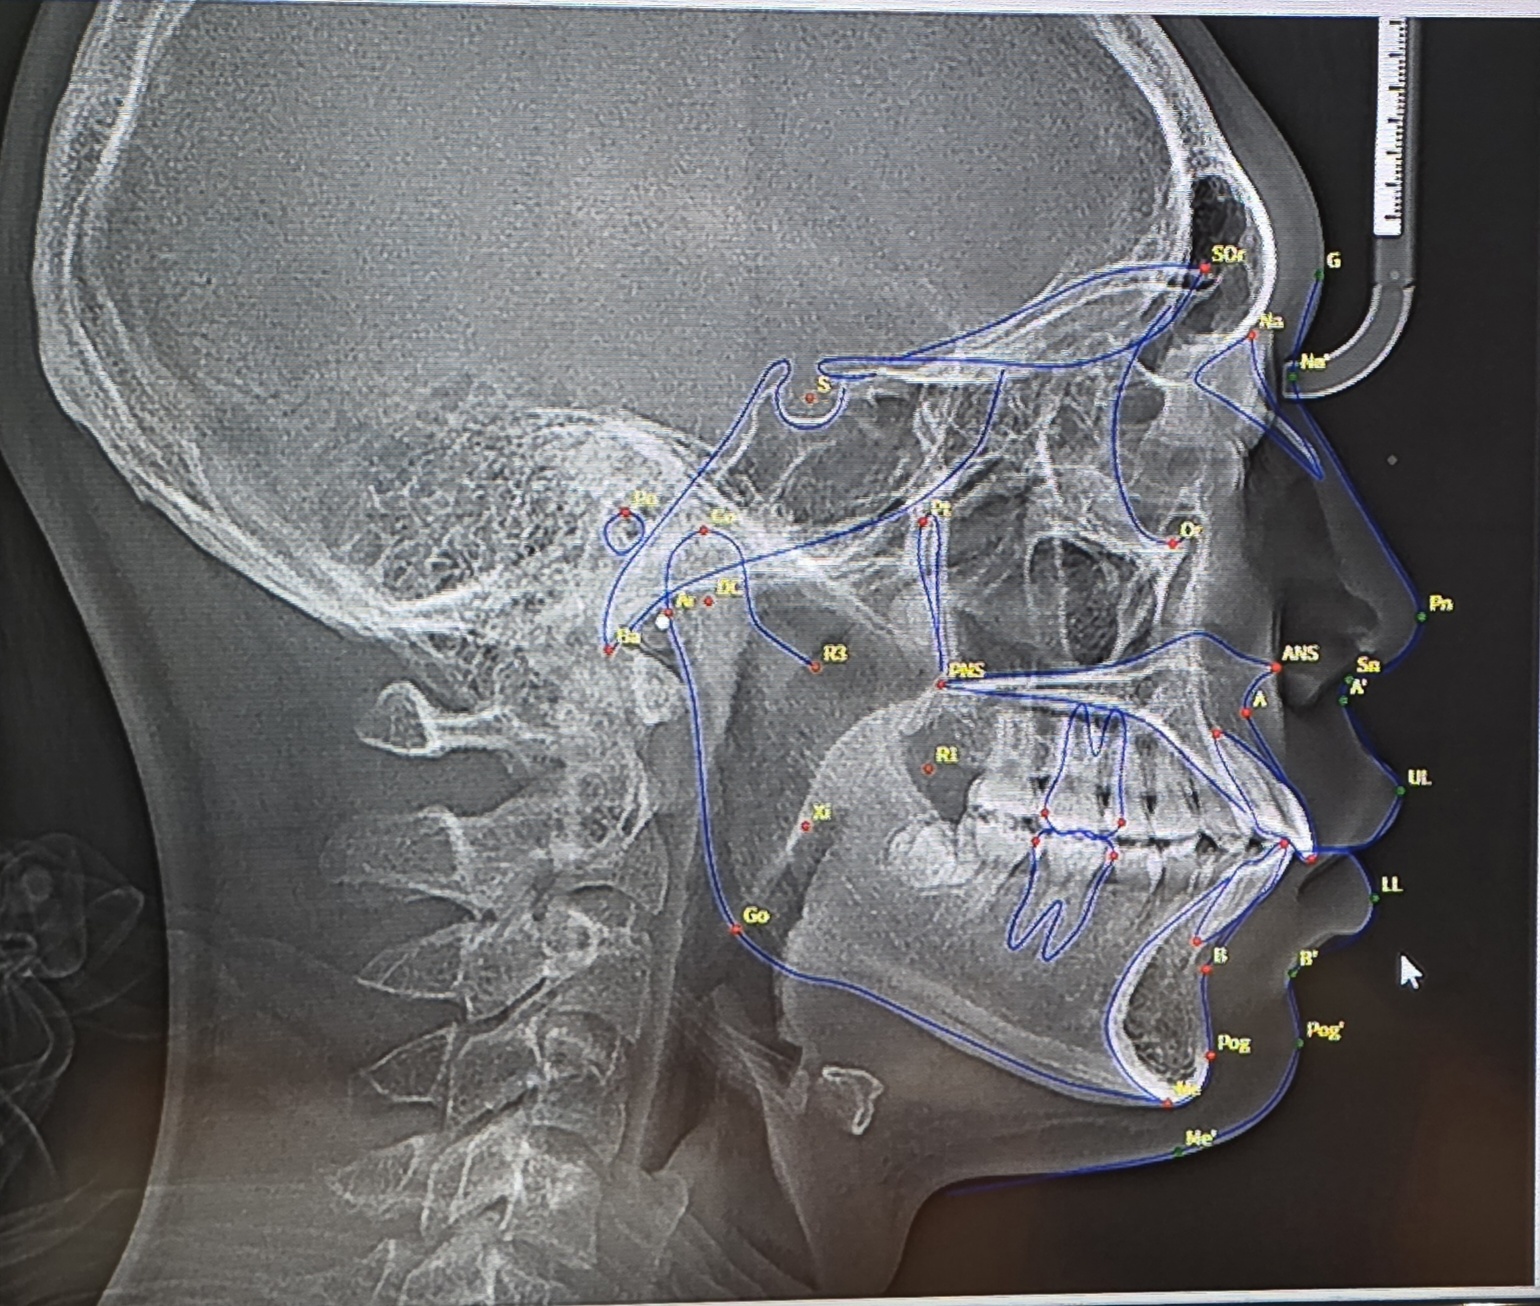

is my maxilla recessed based off of this xray?

ignore overjet